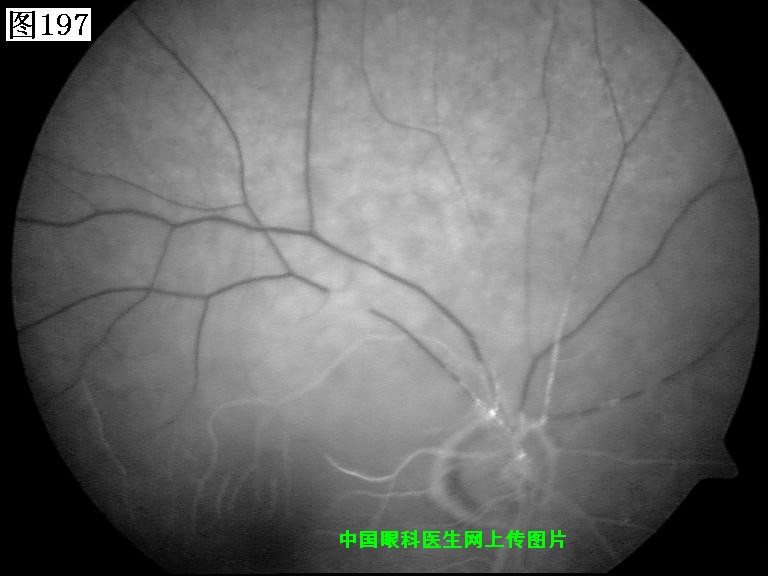

197 198 199 200